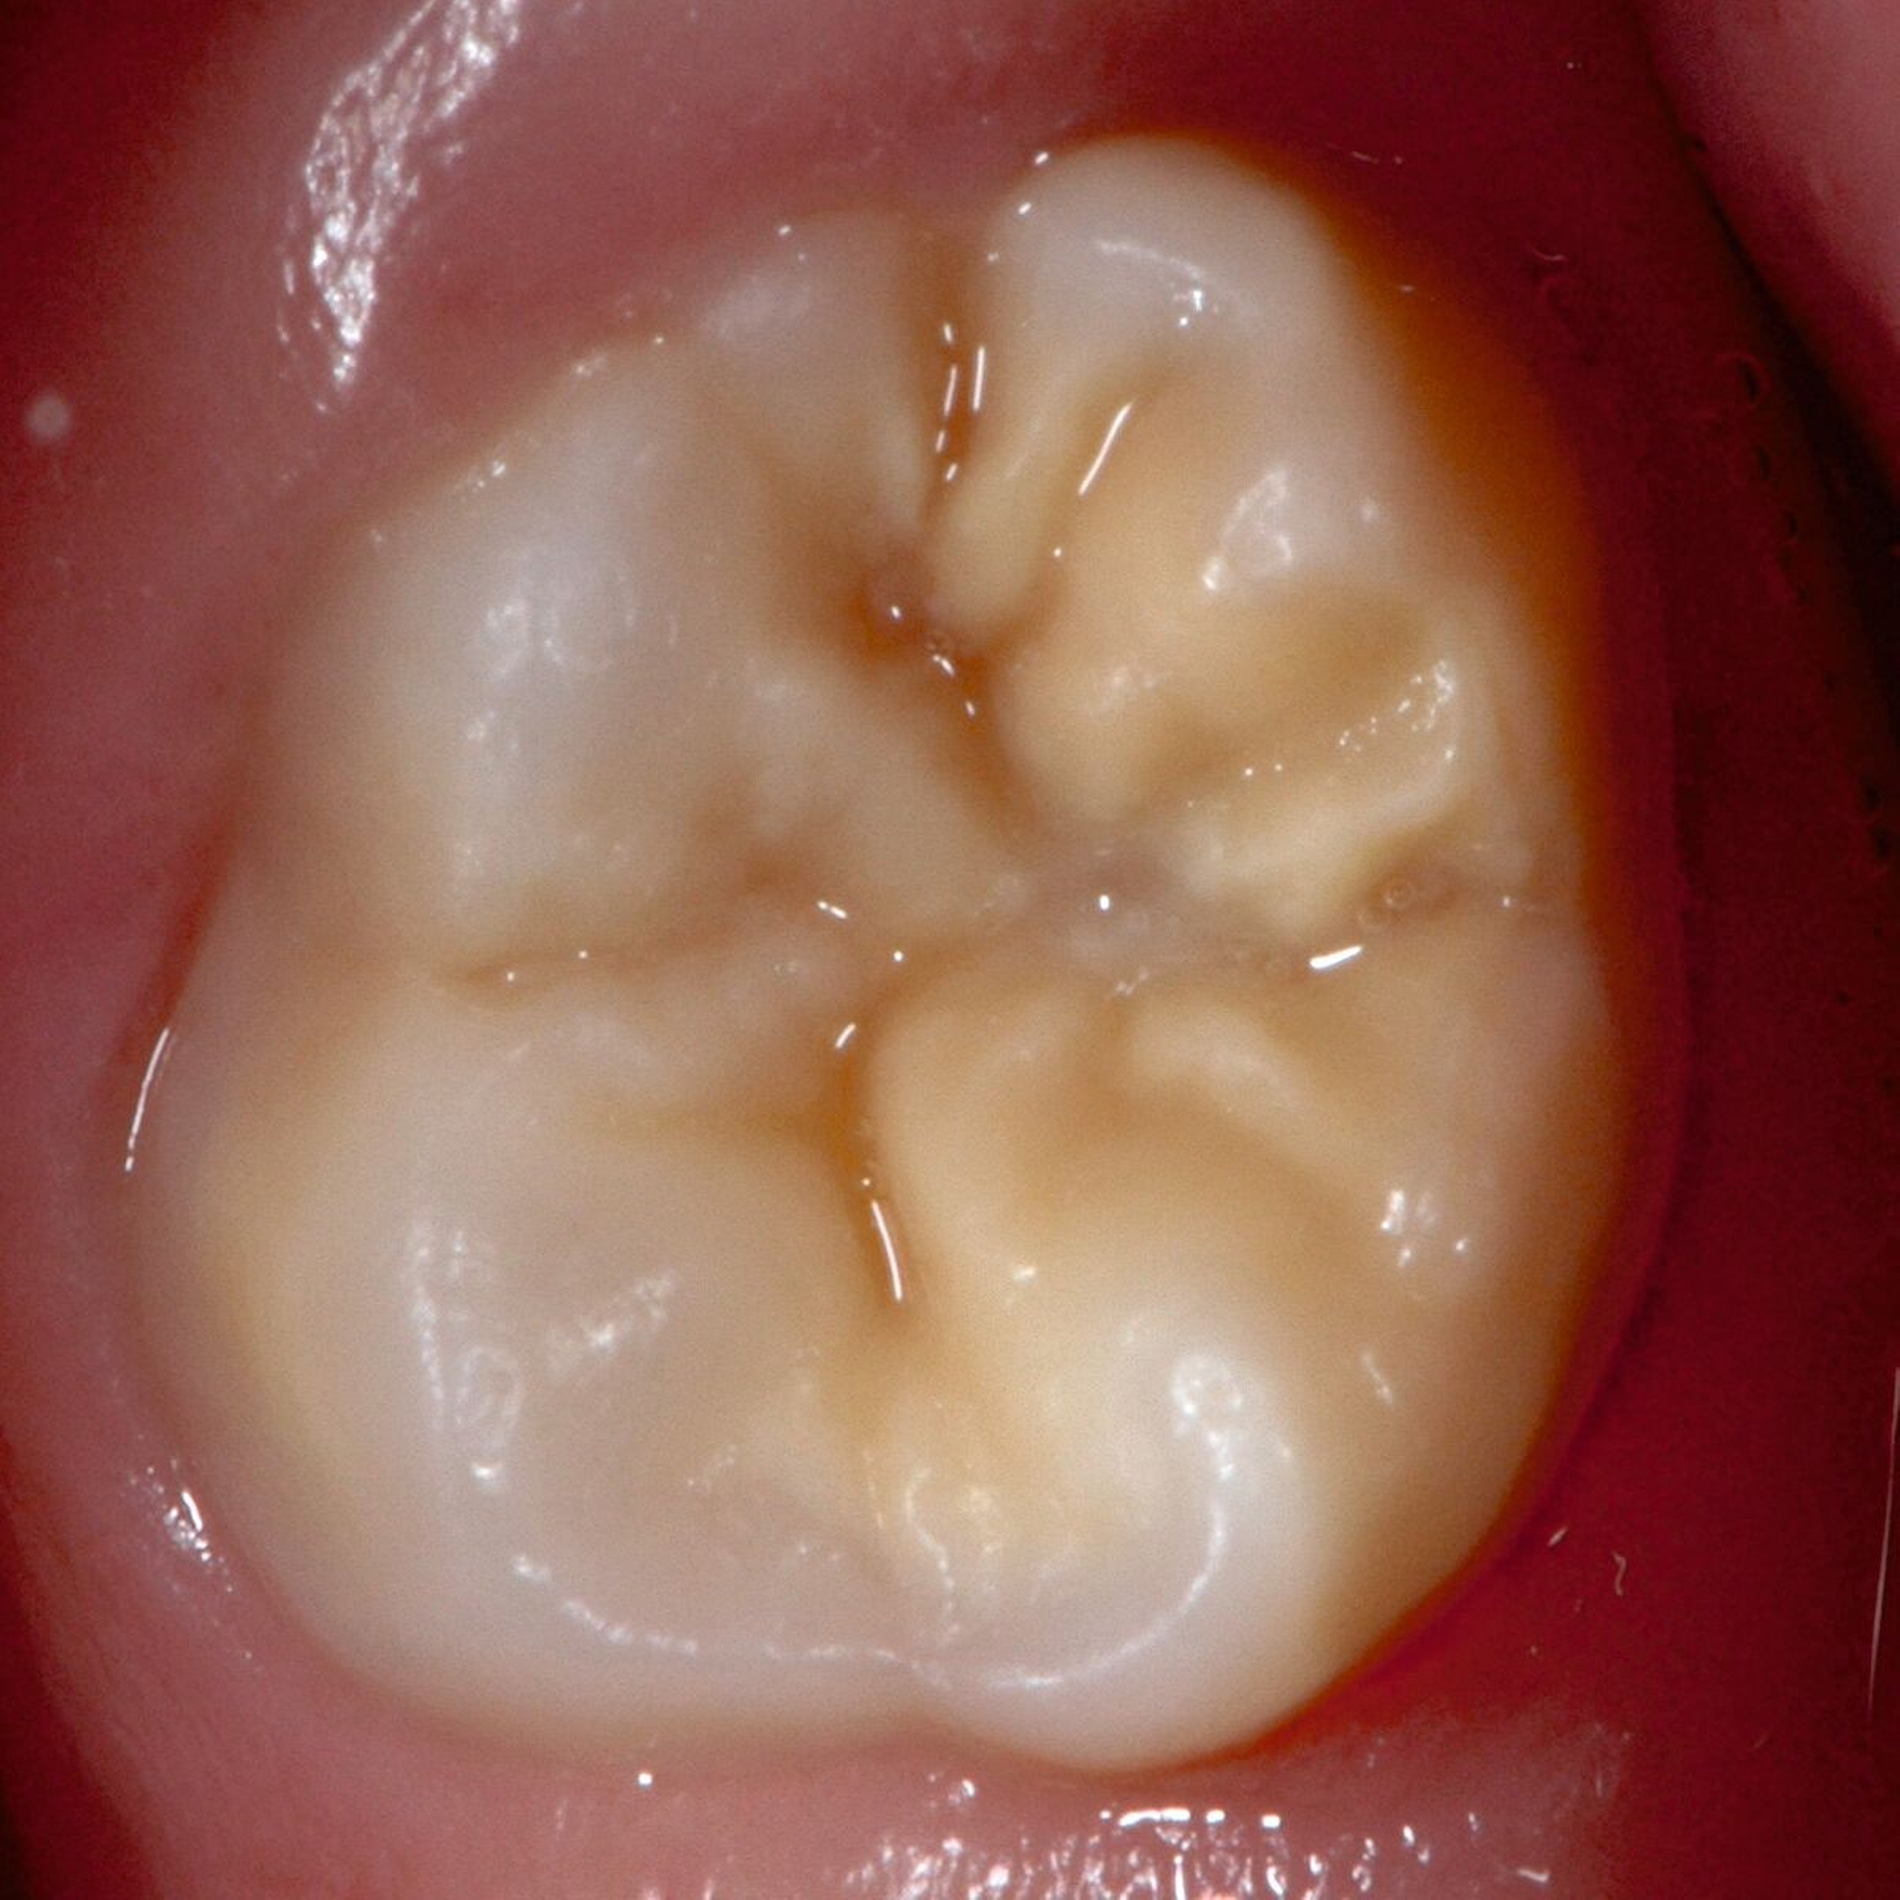

Das klinische Erscheinungsbild an bleibenden Zähnen zeigt typischerweise weißlich-gelbe bis gelblich-braune Opazitäten, die zumindest in einigen Bereichen durch eine scharfe Abgrenzung (engl.:„demarcated opacities“) zum gesunden Zahnschmelz charakterisiert sind (Abbildungen 3 und 4). Die abgegrenzten Hypomineralisationen befinden sich mehrheitlich im Bereich der inzisalen Kronenhälfte unabhängig von dem Auftreten an Front- oder Seitenzähnen. Die Ausprägung am Zahn kann dabei auf einzelne Areale oder Höcker begrenzt sein.

Für die Dokumentation und Klassifikation der MIH wurden verschiedene Systeme vorgeschlagen. Als historisch und veraltet gilt der (modifizierte) DDE-Index. Demgegenüber haben die Kriterien der EAPD – abgegrenzte Opazitäten (Abbildung 3 und 4), Schmelzeinbrüche (Abbildung 5), atypische Restaurationen (Abbildung 6) – mittlerweile die weiteste Verbreitung gefunden. Diese wurden 2003 erstmals zur Beschreibung der MIH auf empirischer Basis publiziert [Weerheijm et al., 2003] und den Jahren 2010 und 2022 im Rahmen der damaligen MIH-Workshops bestätigt [Lygidakis et al., 2010; 2022].